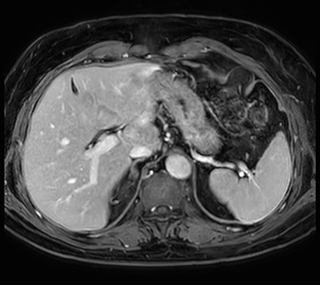

Free breathing abdominal MRI with VitalEye

Ascites can be hard to image, but excellent result is obtained with Ingenia Ambition. This high resolution image demonstrates the high quality that can be obtained with VitalEye and the patient just breathing normally. The acquisition time is fast thanks to the accuracy of the respiratory gating with VitalEye** and it also saves the time needed to put a respiratory belt on the patient.

MCVI VitalEye abdomen

3D T2 with VitalEye

MCVI VitalEye ascites

Abdominal MRI without contrast agent

MCVI Ambition abdominal MRI

Using mDIXON provides excellent fat saturation uniformity. No artifacts seen at the edges in these images, while these were quite commonly seen with eTHRIVE on our previous system. Note also the high resolution.

Ingenia Ambition, 3D breath hold, FOV 370 mm, voxels 1.51 x 1.58 x 4.0 mm, 120 slices, scan time 19.6 sec.